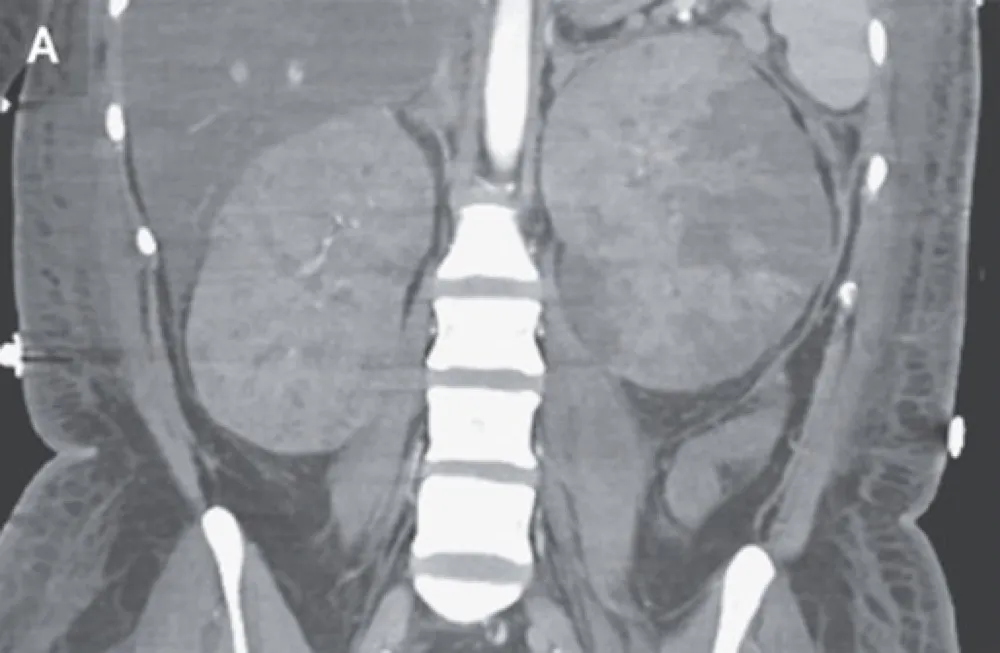

Uma causa incomum de hematúria glomerular intermitente!

Uma causa incomum de hematúria glomerular intermitente!

Hematúria pós infecção, caso clínicos para auxiliar no entendimento de causas glomerulares comuns e raras...